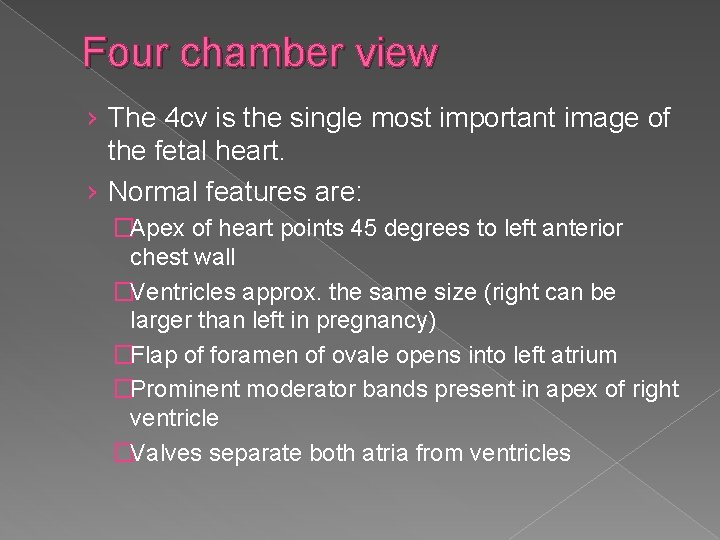

Four chamber view › The 4 cv is the single most important image of the fetal heart. › Normal features are: �Apex of heart points 45 degrees to left anterior chest wall �Ventricles approx. the same size (right can be larger than left in pregnancy) �Flap of foramen of ovale opens into left atrium �Prominent moderator bands present in apex of right ventricle �Valves separate both atria from ventricles

� Normal orientation of the 4 chamber heart view within the fetal chest: the heart should take up 1/3 of the chest cavity with the apex pointing to the left chest wall.